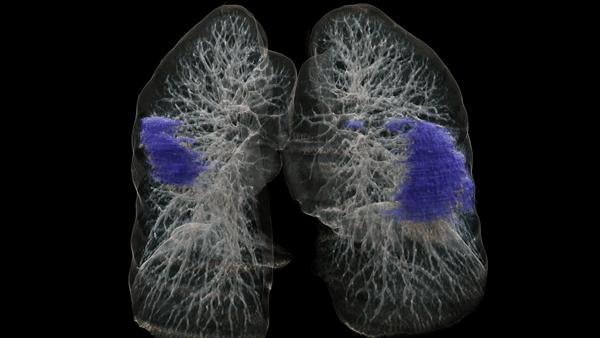

Leading AI scientist Bogdan Georgescu and his team have developed an algorithm that could greatly benefit clinicians in future by helping them to assess COVID-19 severity and progression.

Hot on the trail of COVID-19: Working with collaborators from around the world, a team began developing an algorithm that helps to evaluate changes in lung tissue. Read about how scientists reached a significant milestone during the pandemic.

Solutions that are based on artificial intelligence can ease the workload of radiologists by providing experts with analyses for further assessment. For radiology, this means greater efficiency.